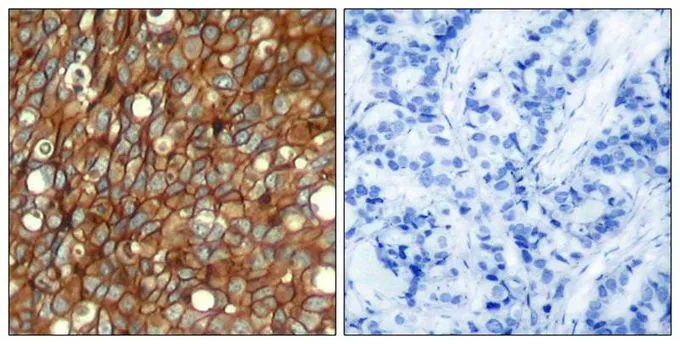

ApplicationsImmunoFluorescence, Western Blot, ImmunoCytoChemistry, ImmunoHistoChemistry, ImmunoHistoChemistry Paraffin

- ApplicationsImmunoFluorescence, Western Blot, ImmunoCytoChemistry, ImmunoHistoChemistry, ImmunoHistoChemistry Paraffin